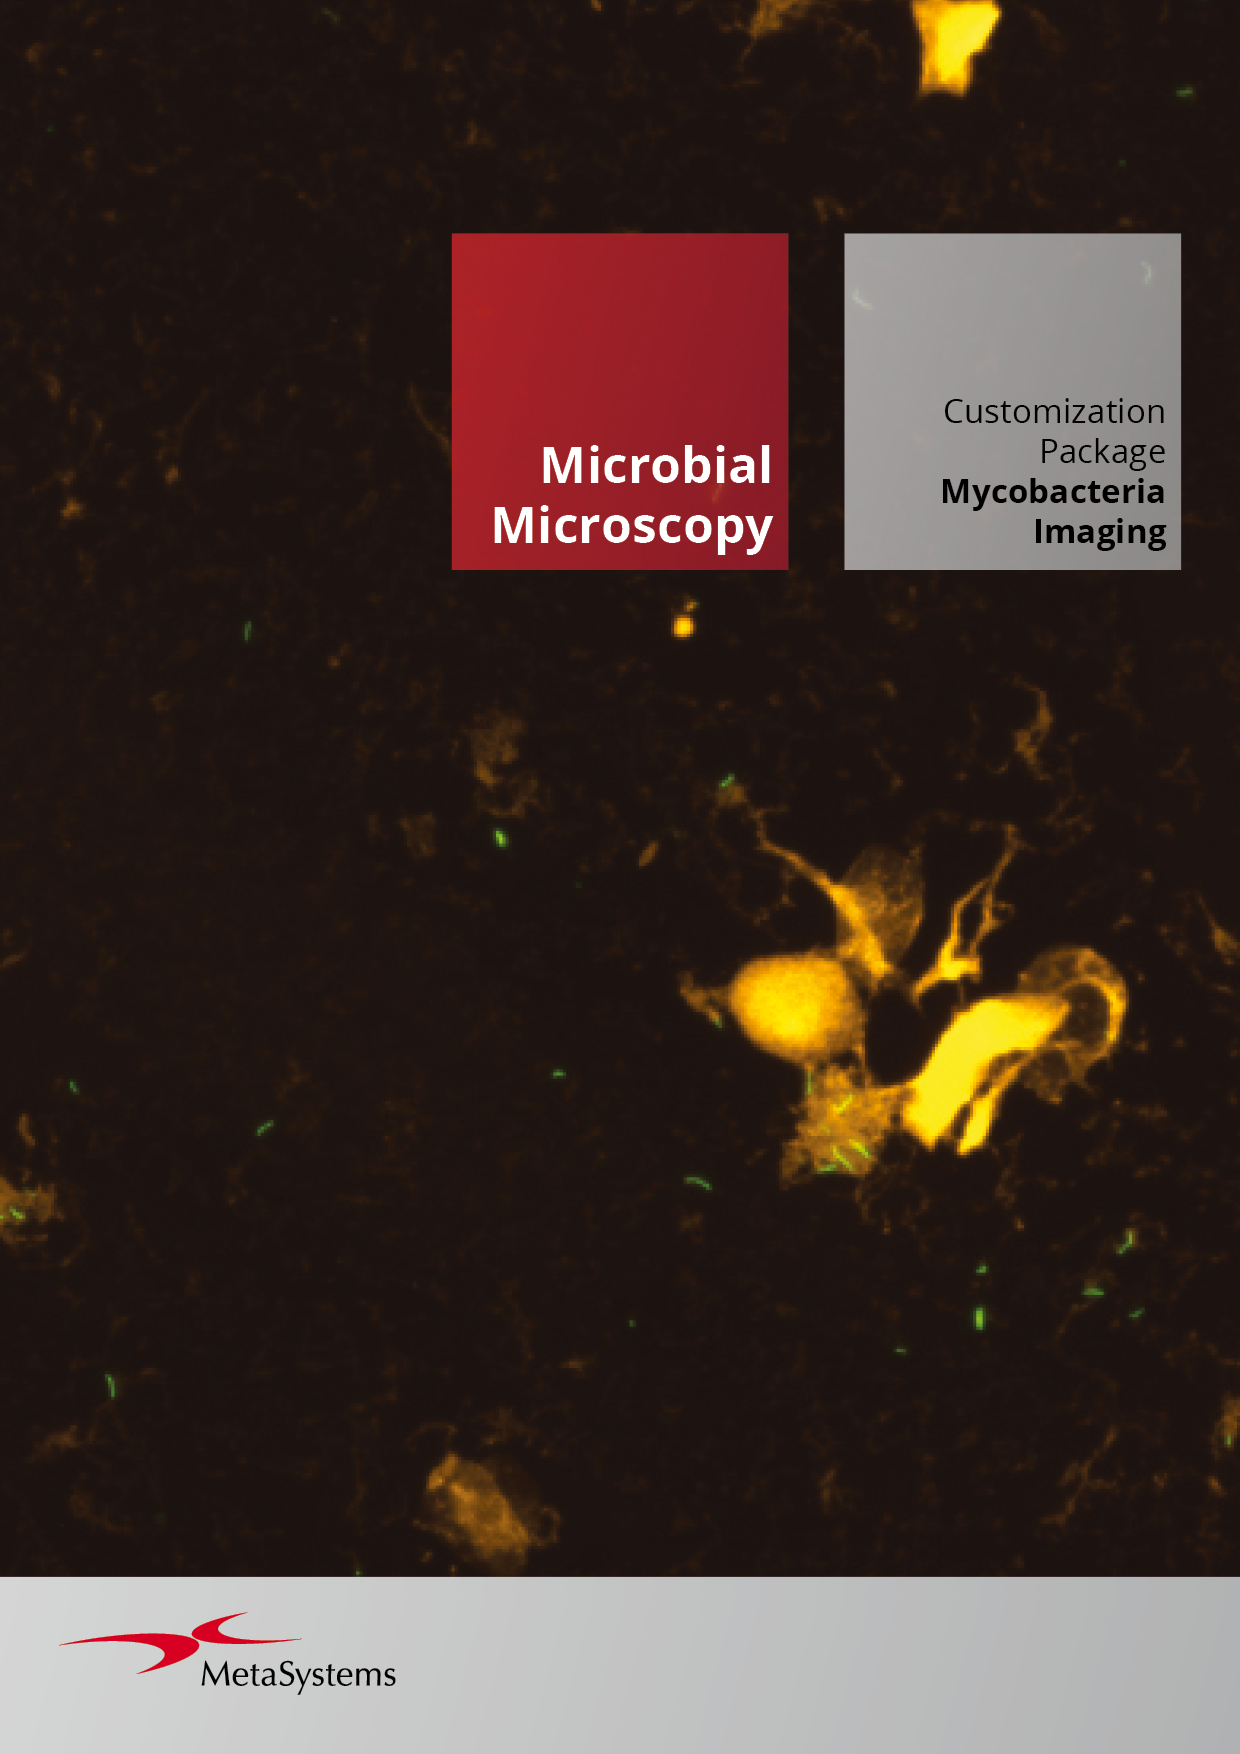

Customization Packages

To help you get the most out of this modular workflow approach, our Customization Packages offer more than a standard setup: they deliver a comprehensive service for configuring Metafer precisely to your task. Drawing on extensive experience from similar installations, our application specialists work closely with your team to define and refine the optimal workflow for your laboratory. This expert support accelerates the path from installation to user validation and routine operation, ensuring a faster, more confident start.

MetaSystems offers Customization Packages for application workflows that have been successfully implemented for customer labs using standard Metafer platform functionality. It is expected that they can be implemented for other customer labs using similar workflows and slide preparation procedures. If a Customization Package is purchased, MetaSystems product specialists will – based on their experience from other similar application cases - support the customer lab in adapting the Metafer software configuration to their needs. The performance of the solution will depend on the quality of the customer slides and the expertise of the users, MetaSystems cannot specify or guarantee any performance parameters. The validation of the solution for clinical use is the sole responsibility of the customer lab.